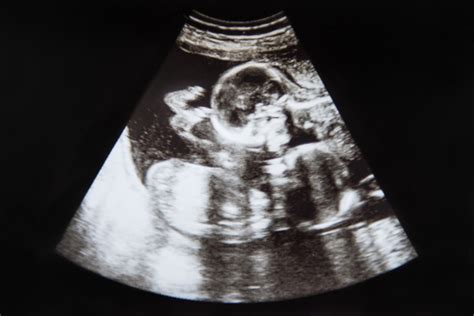

Vývoj a pôrod dvojičiek

Vývoj dvojčiat v maternici je podobný ako pri jednovaječných deťoch, ale rast sa okolo 26. týždňa tehotenstva môže mierne spomaliť v dôsledku stiesnených podmienok. Srdce im začína biť okolo 6. týždňa, v 8. týždni sa začínajú vyvíjať hlavné orgány, tváre sa formujú okolo 12. týždňa, pohlavné orgány sú viditeľné v 16. týždni a od 24. týždňa sa začínajú ukladať tuky a formovať krvné bunky.